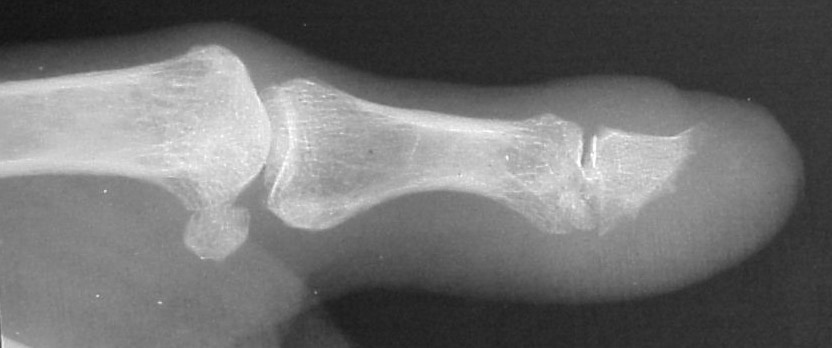

Plain films showed resorption of the distal two thirds of the distal phalanx:

This incorporated, with some terminal resorption: